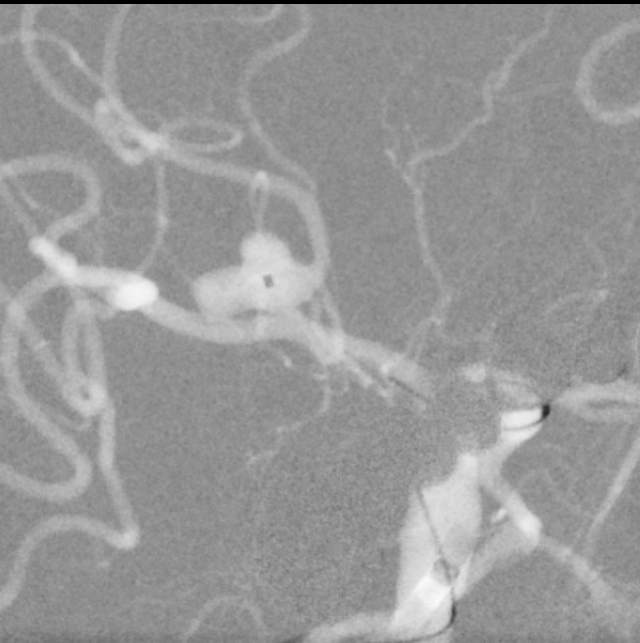

话归正传,下面我们看看如何分兵使用“犄角之势”的策略夹击栓塞“犄角之势”的硬骨头(分叉部绝对宽颈带有俩角的动脉瘤):两个微导管先后到位,两个子囊内的弹簧圈相互依偎,形成“犄角之势”,共同击杀两者之间的大本营(共同的瘤体),最终致密栓塞动脉瘤,消除了动脉瘤再次兴风作浪(再出血)的风险,也最大限度的保全了各个分支血管(粮道)的安全,急性期也没有使用支架,降低了费用,还保障了安全。

栓塞一个复杂动脉瘤,就是进行一场战争。采用“犄角之势”致密单纯栓塞动脉瘤后,指挥者(术者)没有支架内血栓的顾虑,也不担心再出血的侵扰,还有止血药、降压药的保驾护航,可以安心班师回朝了~~~